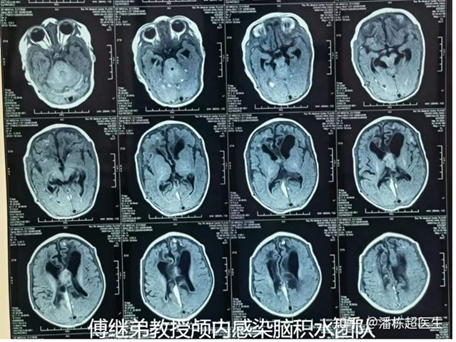

这个宝宝出生后13天发生颅内感染、脑脓肿,同时继发了脑积水。由于脓液破入脑室,引起化脓性脑室炎危及生命,多次腰穿鞘内给药都没有办法控制感染。而孩子的头围,也因为脑积水的持续加重而增大,骨缝都哆开。

巨大脑脓肿、化脓性脑室炎、重度脑积水

最后他来到中国医学科学院傅继弟教授颅内感染脑积水治疗组,我们内部讨论了孩子的病情,给出了一个同时解决颅内感染、脑积水的方案。此时距离最初发生颅内感染已经过去了40多天,这40多天孩子都是在ICU内度过。

脑室-腹壁长程潜行体外引流,骨缝哆开,头围增大

术后给予脑脊液净化引流治疗,用了一周多控制住活动性感染,一个月的时间,脓肿大部分吸收。孩子的脑组织也开始复张,并恢复到接近正常,此时孩子的各项生理指标也都在快速恢复。

脓肿大部分吸收,体温正常,脑组织厚度恢复

经过2个多月,70多天的治疗,颅内脓肿基本完全吸收,脑脊液指标也趋向于稳定,感染也没有复发的迹象。在这个前提下,终于可以给他结束治疗。而此时的这个小患者,身体的各项机能、反应能力也已经和正常同龄孩子没有差别。